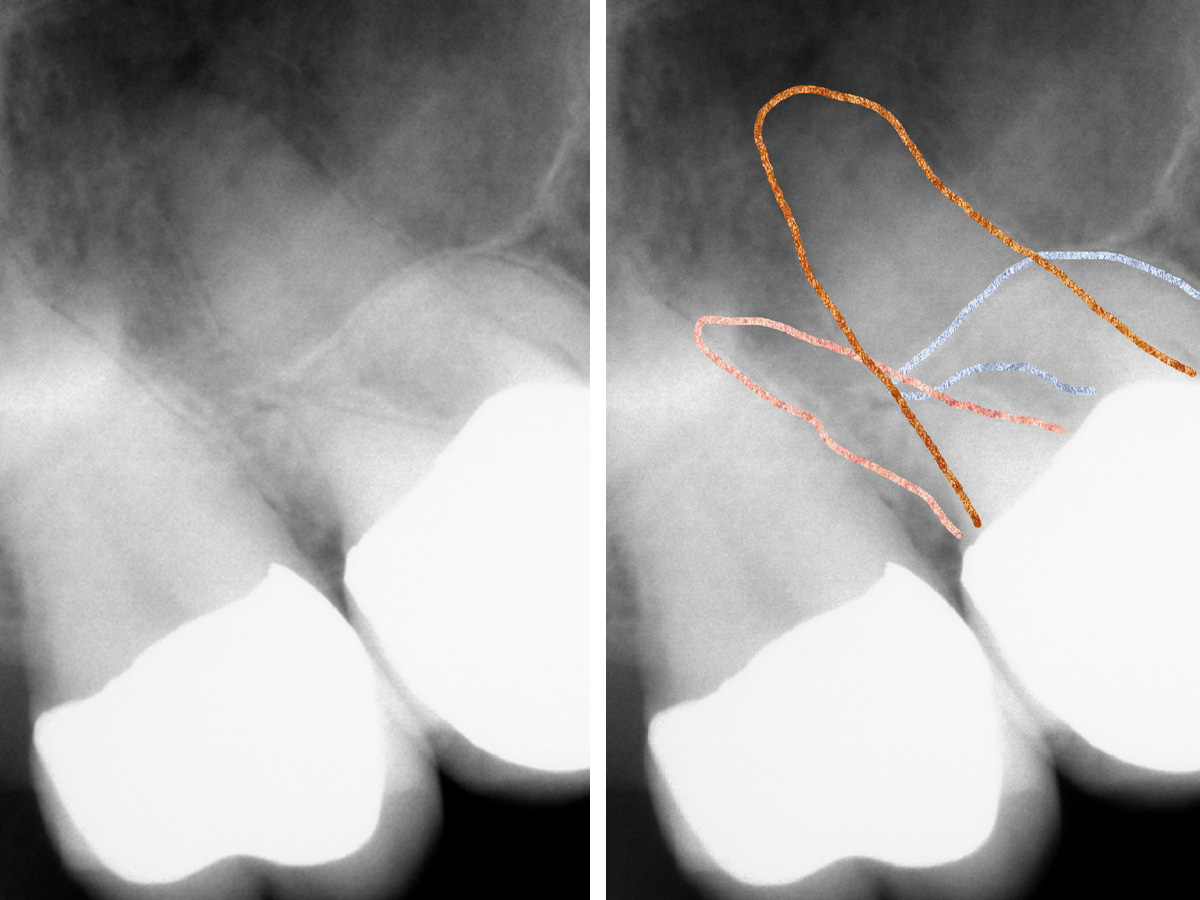

Abbildung 1

Röntgenologisch (Einzelbild 16-17) sind zwei Einzelkronen erkennbar. Keine zusätzliche diagnostische Information.

Abbildung 2

Nach der DVT-Untersuchung (Kodak 9000 3D, Auflösung 0,076 mm) bestätigte sich eine apikale Parodontitis an Zahn 16 palatinal. Eine Wurzelkanalbehandlung an Zahn 16 ist indiziert.